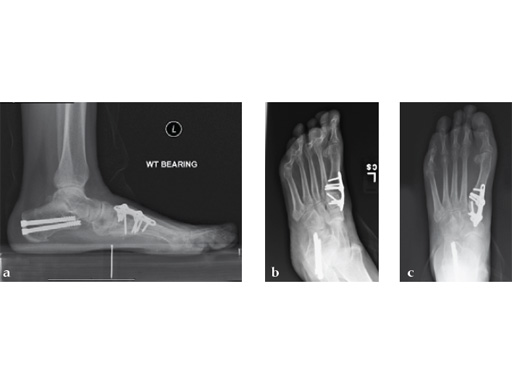

Case 2: First MTP fusion plate

A 38-year-old man presented for opinion after two attempts to fuse the big toe MTP joint. The AP view is significant for luscency at the joint line. The lateral view is notable for loosening of the hardware and malposition because of the dorsiflexion built in to the precontoured implant. Revision was planned using a 0 variable angle locking/compression hallux MTP plate.

Case provided by Michael Castro, Scottsdale, Arizona

At 10 weeks postoperatively (see Fig. 2ab) the patient had no pain with weight bearing. The lateral view demonstrates improved position of the toe using a 0angle plate.